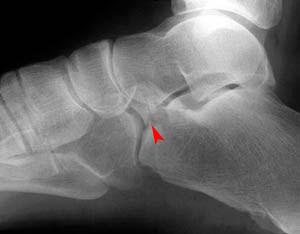

Calcaneal Fracture Classification